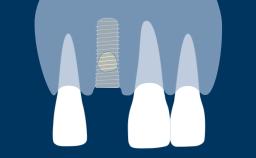

Fatores múltiplos influenciam o sucesso de cirurgias implantares. O que incluem planejamento cuidadoso do tratamento a ser realizado, conhecimento básico de técnicas cirúrgicas comuns a todos os procedimentos cirúrgicos e habilidade de executar estes procedimentos de maneira atraumática. Um destes procedimentos é o fechamento de qualquer retalho gengival que foi rebatido durante a cirurgia. O objetivo do fechamento de retalhos tecidual é reposicionar os tecidos moles gengivais em uma posição anatômica adequada. O fechamento satisfatório do retalho cirúrgico tecidual promove a cicatrização e reduzir complicações como abertura, deiscência e infecção da ferida. Esses fatores desempenham um papel importante na obtenção de resultados cirúrgicos bem-sucedidos e estéticos. Este módulo se concentrará no fechamento do retalho gengival para cirurgia oral relacionada aos procedimentos de implante.

- descrever os princípios cirúrgicos do fechamento de retalhos gengivais após cirurgias implantares